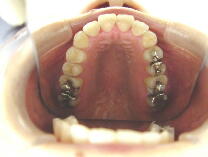

症例3 (30代 女性) 右下顎切歯先天性欠如

左右上顎第一小臼歯・右下顎第一小臼歯抜歯例

初診時